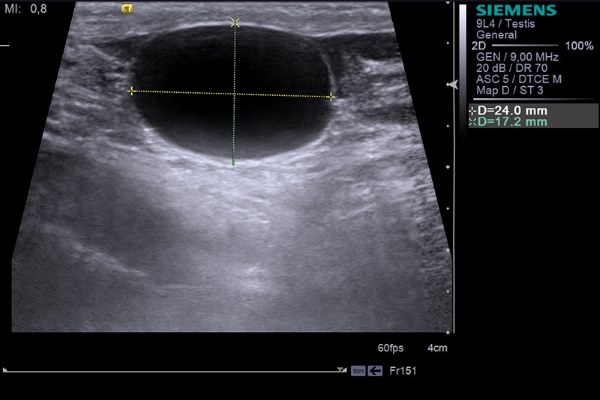

Объем мочевого пузыря на УЗИ

Объем мочевого пузыря измеряют при позыве на мочеиспускание. На продольном срезе измеряют максимальную длину от шейки до дна мочевого пузыря. На поперечном срезе измеряют толщину — максимальный передне-задний размер и ширину мочевого пузыря. Объем вычисляют по формуле для эллипсоида вращения: Длина*Толщина*Ширина*

0,523.

Рисунок. Объем мочевого пузыря.